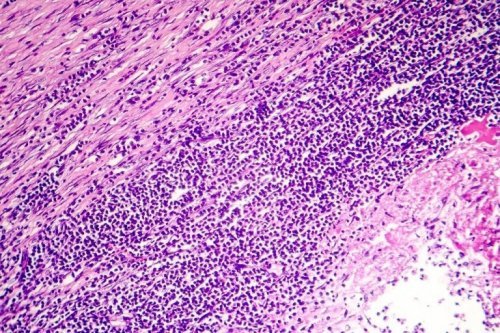

A pericardite é a inflamação do pericárdio. O pericárdio, em suma, é uma membrana em forma de saco que rodeia o coração. Esta membrana tem duas camadas e entre ambas existe um pequeno volume de líquido, que serve como lubrificante e faz com que as duas camadas deslizem entre si, sem causar problemas.

A pericardite crônica acontece quando se forma, previamente, um tecido fibroso ao redor do coração. Em suma, este tecido comprime esse órgão e aumenta a pressão nas veias que levam o sangue até ele. Isso faz com que o líquido do pericárdio se estanque e, em sua tentativa para sair, termine acumulando-se em outras partes do corpo.